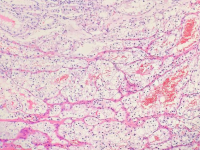

王功伟老师肾脏肿瘤系列讲座(十五):

王功伟

北京大学人民医院病理科